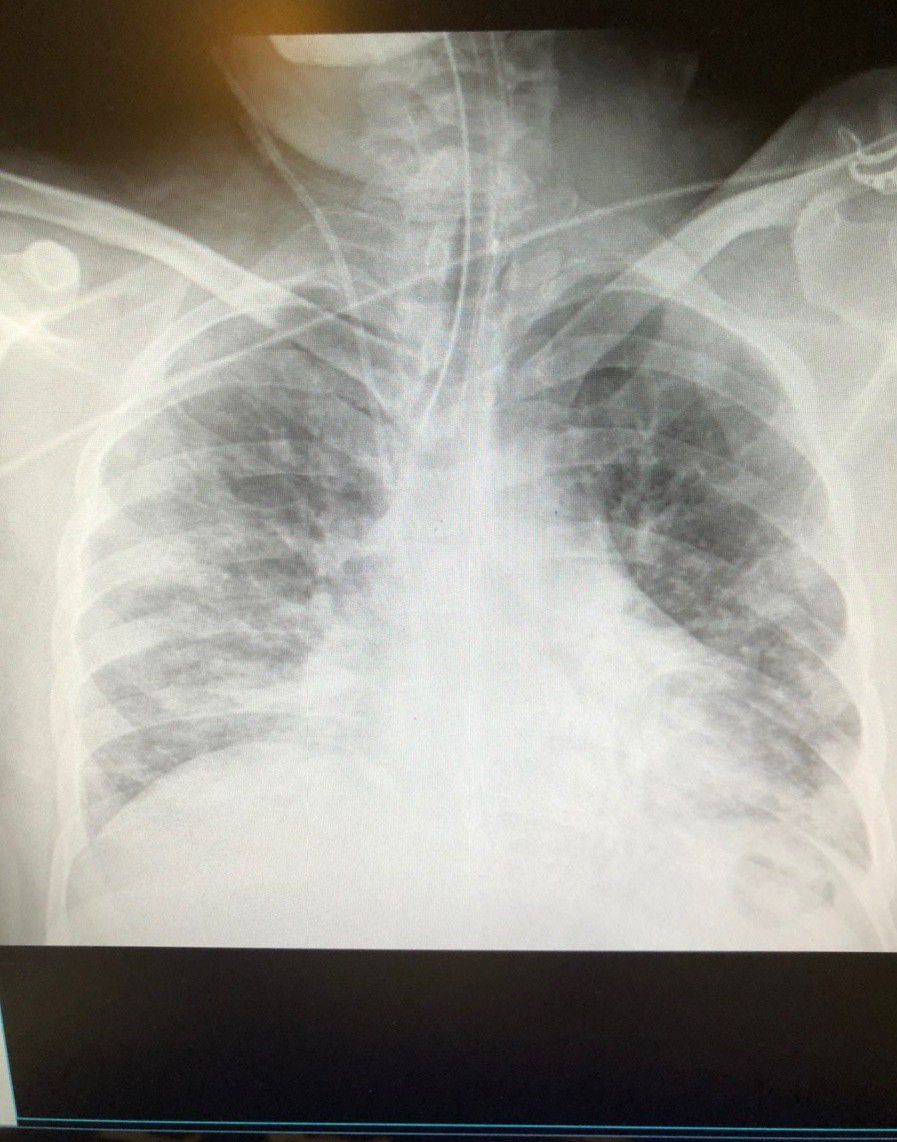

1.Both lungs shadow decrease translucency 2.pulmonary vascular markings are prominent 3.cardiac shadow is increased.Boot shaped heart. Acute pulmonary oedema. Due to hypertension.